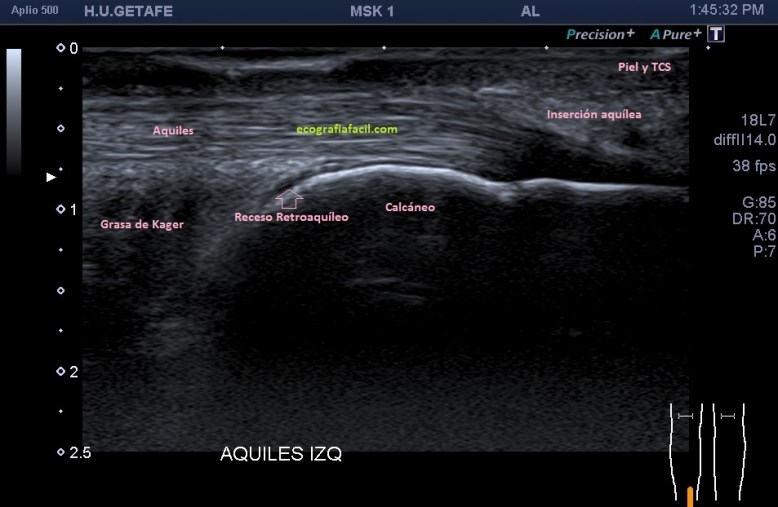

El Aquiles es el tendón de los gemelos y el sóleo que inserta en la cara posterior de la pierna, en el calcáneo. Sus fibras son alargadas, es un tendón muy potente, muy superficial, ecogénico, superficial a la grasa de Kager.

Posicionamos al paciente en decúbito prono, los pies colgando al final de la camilla, y haciendo una hiperflexión dorsal del pie tobillo con el fin de tensar el Aquiles, gel y sonda de alta frecuencia y empezamos.

En el texto anterior hemos visto enmarañadamente muchos conceptos asociados a patologías que pueden darse en esta pequeña región del Aquiles. He nombrado el Síndrome de Haglund. Este es un síndrome que incluye tres aspectos, a nivel del aspecto posterior del calcáneo con una afectación de la bursa retroaquílea debido a la presencia de una exóstosis.

En muchas ocasiones vamos a encontrar calcificaciones de inserción o entensopatías, pero ver ecográficamente la afectación de la bursa es mucho menor. En muchas ocasiones, la radióloga necesita ampliaciones de estudio con radiología simple y con RMN para poder efectuar convenientemente este diagnóstico y nosotros, tenemos que ser muy minuciosos en la exploración ecográfica de esta región, conocer perfectamente ecoarquitectura normal de la región para poder identificar tanto los calcios insercionales como la bursitis retroaquílea, amén de la tendinopatía, ni que decir tiene a complicaciones tendinosas derivadas de estado avanzados de la patología como pudieran ser la roturas insercionales, parciales o totales.

Si observamos la bursitis retroaquílea de la imagen 11(flechas amarillas), además la exóstosis de la imagen 13 y deformidad en la piel, observable sin ecografía podemos estar ante un síndrome de Haglund de esos de libro…y tendremos una imagen ecográfica como la de la imagen 14.

En la imagen 14, como no podía ser de otra manera, observamos todo y es por definición la típica imagen de S.Haglund.